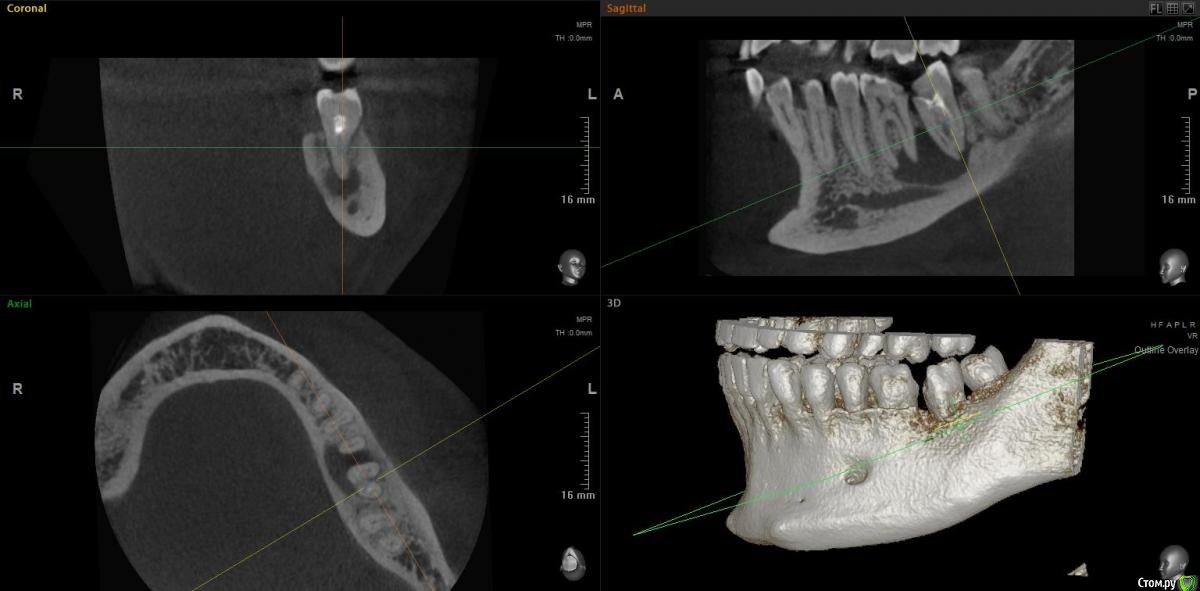

jm3300 Опубликовано 15 ноября, 2020 Поделиться Опубликовано 15 ноября, 2020 Коллеги, можно в данном случае вытянуть консервативно? Ссылка на комментарий

Irouil Опубликовано 15 ноября, 2020 Поделиться Опубликовано 15 ноября, 2020 Тут, похоже, не(только) корневая киста, язычно карман. Вопрос в терапию, наверное, но я скажу - нет 1 Ссылка на комментарий

red_butler Опубликовано 15 ноября, 2020 Поделиться Опубликовано 15 ноября, 2020 Имхо нужно в терапию, по данным срезам не увидел проблем с реэндо 2 Ссылка на комментарий

jm3300 Опубликовано 15 ноября, 2020 Автор Поделиться Опубликовано 15 ноября, 2020 Тут, похоже, не(только) корневая киста, язычно карман. Вопрос в терапию, наверное, но я скажу - нетвозможный карман тоже смущает Ссылка на комментарий

Дмитрий М Опубликовано 15 ноября, 2020 Поделиться Опубликовано 15 ноября, 2020 самого пациента ещё не видел. попросили КТ посмотретьок )) тогда понятноесли только из снимков то 36 пробовать сохранять, эндо и наблюдение а вот 37 больше за удаление был подобный случай, только киста немного меньше была но так же с вовлечением корней 36 и 37 терапевт хотела удалить оба, но решили оставить 36 полечить и наблюдать, а 37(разрушен не подлежал восстановлению) удалил, кисту почистил, ч/з 3 мес имплант. в итоге с 36 все хорошо 1 Ссылка на комментарий